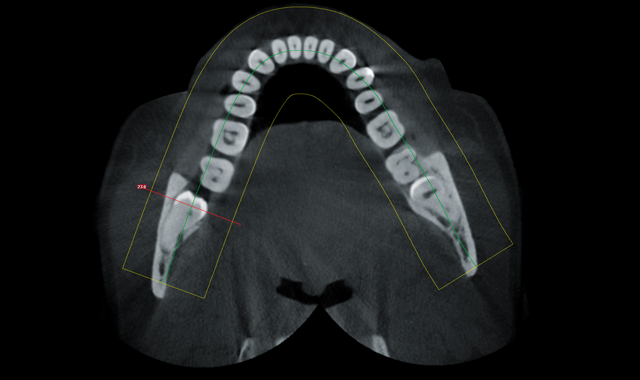

Axial view

After seeing the large lesion on the extraoral bitewing associated with #32 tooth the patient quickly consented to a 3D CBCT of both lower third molar areas.

Coronal view showing proximity of nerve and coronal portion of tooth

Coronal view showing extent of lesion and proximity of nerve and apical portion of root

Through the use of 3D imaging, the patient had a much better understanding of the complexity of the issue. The coronal view of the #32 tooth shows the involvement of the lesion and the distance from the nerve to the coronal portion of the tooth. The improved distal slice shows the extremely close proximity (of lesion) to the mandibular nerve and the apical portion of the root.